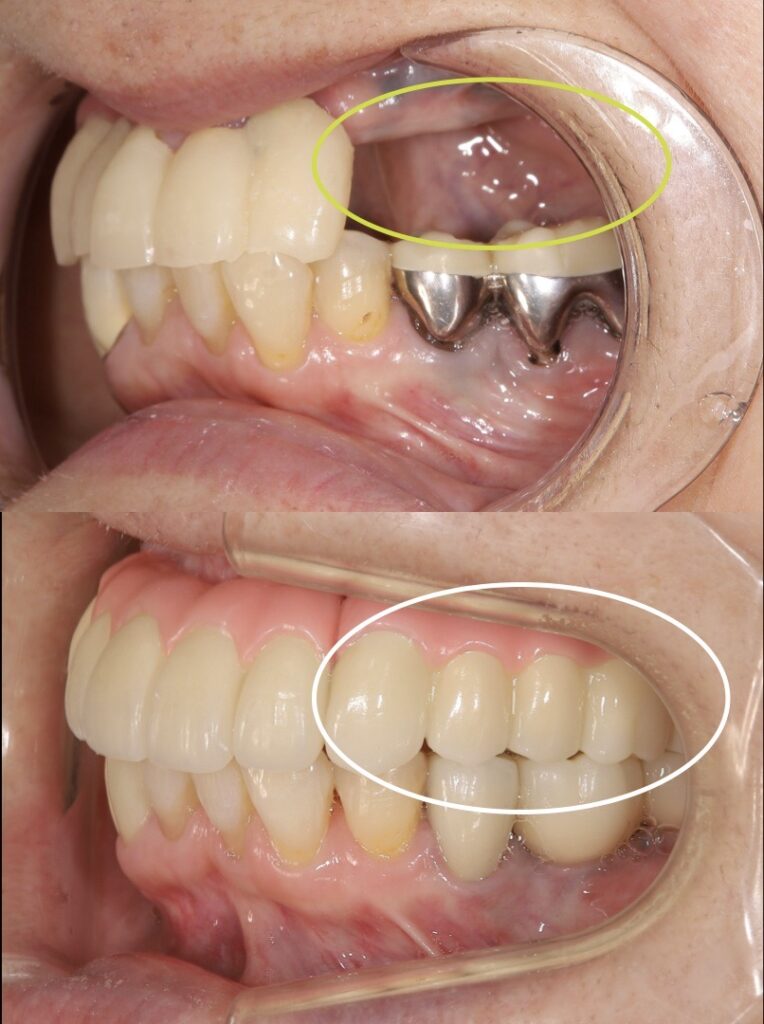

治療前後の横から見た写真

左上の歯が入っていることが見てとれます。インプラントは3本で上の被せ物は5本で噛めるようになりました。

治療前後の写真

左上の奥歯に綺麗なセラミックのインプラントを入れることができ、患者様も入れ歯と比較にならないほどよく噛めるとおっしゃって頂きました。